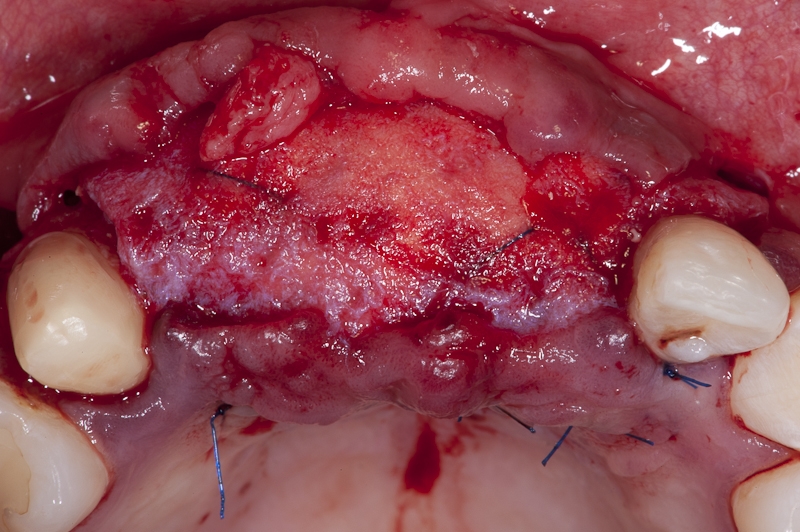

09/17 - Additional protection of the block with cerabone® granules and placement of mucoderm® as barrier membrane and additional soft tissue augmentation in one step